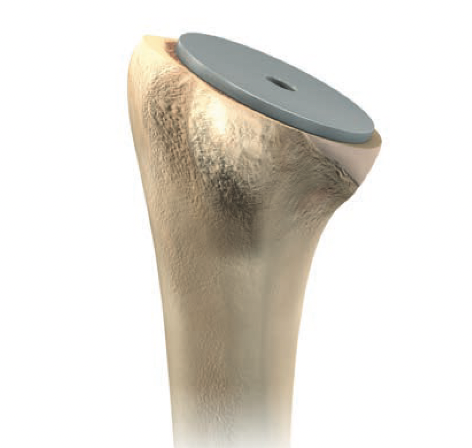

Humerus preparation

Depuy Synthes Delta Xtend

Use cutting guide for neck cut angle

Set retroversion 20°

Inlay verus onlay

Leave trial stem in to prevent fracture